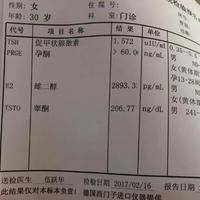

问题描述:今天刚做了取卵手术,过几天就要做移植手术了。按照医生的建议在这之前要去医院做移植前的身体状况检查。从结果来看我雌激素很高,虽然我知道移植对身体状况有严格要求,因此想问问这个情况下能移植鲜胚吗?最佳回答:一般移植鲜胚要求雌二醇水平在6000pg/ml之内。如果在移植前该激素高于正常值的话,很可能会影响到内膜成长、影响到激素平衡继而降低着床成功率。每个试管女性在移植前医生都会要求其做详细身体...